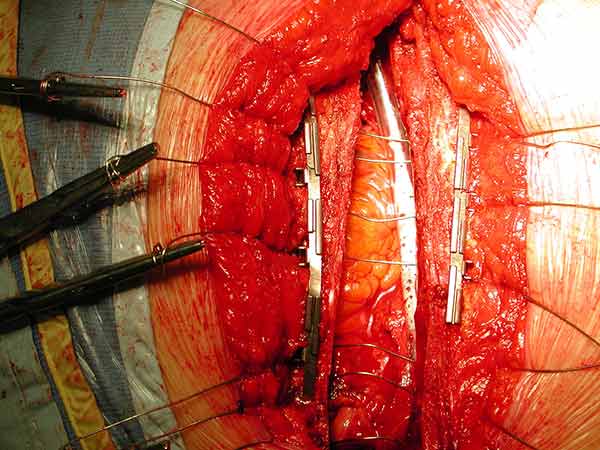

From December 2004 to December 2007, the DSS was implanted in 55 patients in our institution. Of those, 45 patients had at least three preoperative risk factors or experienced bone fracture or paramedian sternotomy detected intraoperatively, and underwent primary sternal reinforcement with the DSS. Of these patients, 75% were diabetic, 50% had chronic obstructive pulmonary disease, and 38% were obese [7]. Only one patient experienced a superficial wound dehiscence. The other 10 patients underwent sternal reconstruction following sternal dehiscence (Figures 11, 12).

Figure 12. Postoperative sternal reconstruction showing sternal fixation with DSS (2 and 3 units in the right and left hemisternum, respectively